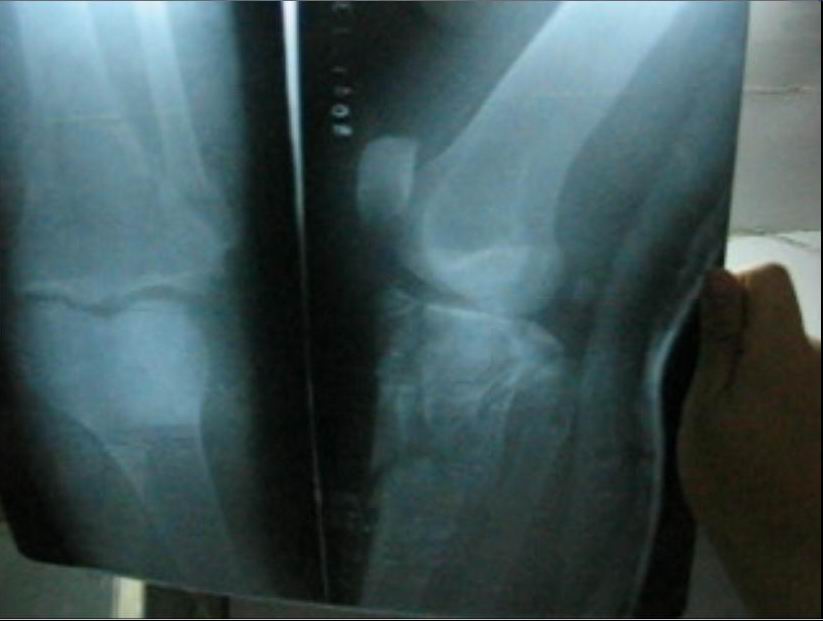

下面是焦龙的腿摔骨折后的照片。

焦龙下来时不慎把左腿摔成粉碎性骨折。被抓后因不能行走,恶警就拽着焦龙的胳膊在地上拖着走,一直拖进车里,他们并没有把他送进医院,而是拉到了团结路派出所,下车时他们还是拽着胳膊在地上把焦龙拖进屋里,并开始对他非法审讯。恶警董某甚至用脚踢他受伤的腿。

而后他们把焦龙送到大庆医院拍片子,拍完后发现多处骨折。从医院他们用车把焦龙拉回派出所,没让他下车。说市里来人正在开会研究,后来出来一位领导模样的人对他说:我们放你走,在大庆有没有亲朋好友,把你接回去治伤。

这样焦龙被出租车司机送走。因为耽误及时救治,他的腿肿得象小水桶一样粗,脚肿得也很高。后来辗转来到外地,直到现在他的腿还没有恢复正常。